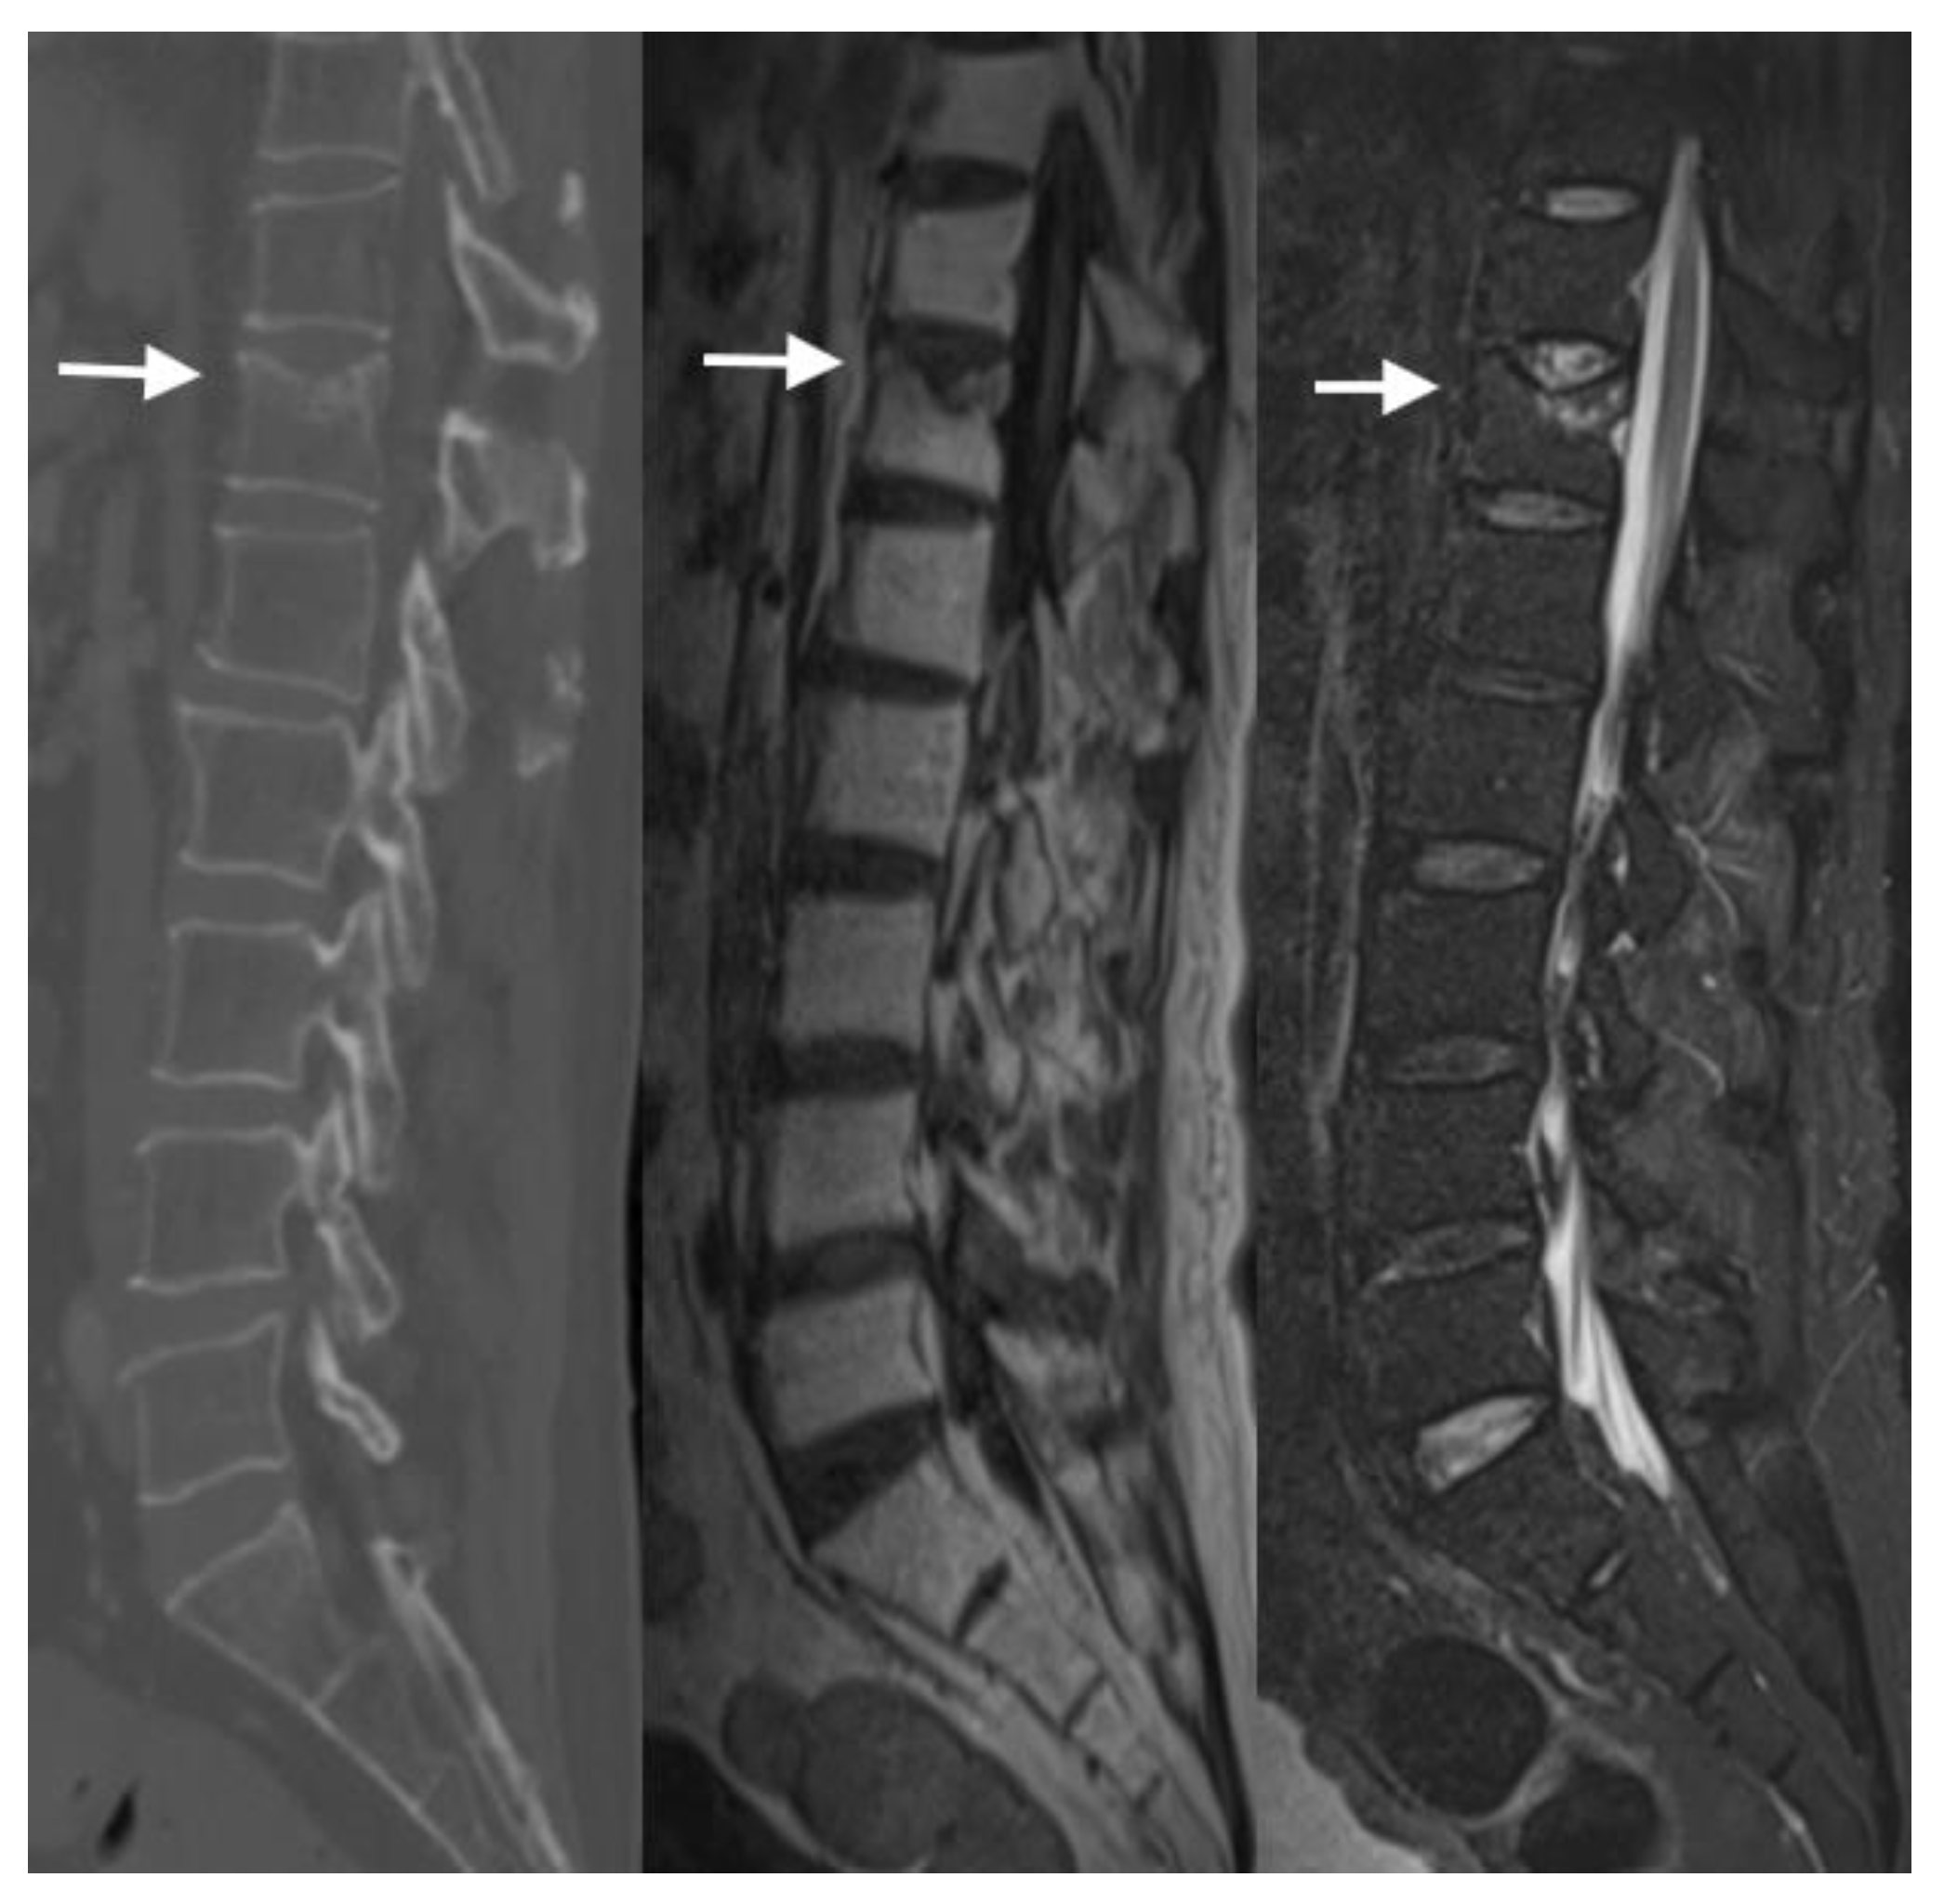

4.2. CT Scans

4.3. MRI Scans